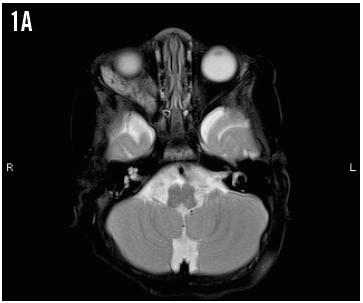

A 2-year-old girl presented with a 1-day history of high-grade fever, cough, and rhinorrhea. She was lethargic and had decreased oral intake. She had no sick contacts or choking episodes.